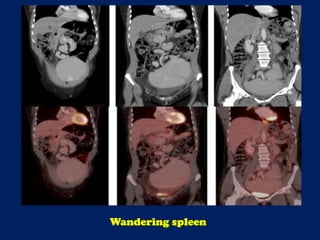

![Axial reconstructions derived from the CT portion of the PET/CT demonstrate the

‘whorled-appearance’ of the long vascular pedicle extending to the ectopic spleen.

The alternating bands of hypodensity and hyperdensity represent the splenic

vessels and surrounding fat of the twisted splenic pedicle. [red arrow = splenic

artery; yellow arrow = pancreas; white arrow = splenic vein; asterisk = spleen]

This document discusses imaging of the spleen and summarizes various congenital anomalies and pathologies that can affect the spleen. Some common congenital anomalies mentioned include accessory spleens, asplenia, polysplenia, and splenic fusions. Acquired conditions like repeated infarctions, infiltration, tumors, and cysts can also cause splenomegaly or functional asplenia. Wandering spleen is discussed as a rare congenital anomaly where the spleen lacks attachments and is mobile within the abdomen. Various grades of splenic lacerations and examples of splenic imaging findings are also briefly summarized.